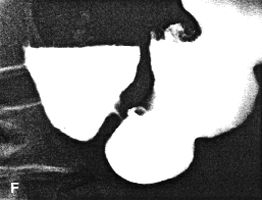

Case 37.1. D.R., 40 year old male had a long history of ethanol abuse and insulin- dependent diabetes mellitus which had been treated inadequately. For several weeks there had been dyspepsia, loss of appetite and nausea. Radiologically primary and secondary oesophageal peristaltic waves were normal. After an overnight fast the stomach contained food residues; the pyloric aperture was patent, measuring 9.0. mm in diameter (Fig. 37.1A). Gastric peristaltic waves were decreased both in frequency (i.e. less than 3 per minute) and intensity (i.e. failing to "bi-sect" the organ). The pyloric sphincteric cylinder was in a state of partial contraction most of the time (Fig. 37.1B). Cyclical contraction and relaxation of the cylinder, normally occurring at a frequency of 3 per minute (Chaps. 13, 15), was lacking. No obstructing lesion was seen at the pylorus and the duodenum appeared normal. Sonographically the gall bladder, liver, spleen and kidneys were normal; there was no ascites. The patient refused endoscopic examination.

| Fig. 37.1. A,B. Case D.R. A Food residues in stomach. Pyloric aperture patent. Gastric peristaltic activity diminished. B Pyloric sphincteric cylinder (arrows) contracted most of the time. |

| Fig. 37.1. C-F. Case D.R. After treatment and clinical improvement. Lessened contraction of sphincteric cylinder. Some movement evident but normal cyclical activity absent. Note pancreatic calcification | |

Six months later, after proper diabetic control, he had improved clinically. On this occasion the stomach contained less residual food. Shallow gastric peristaltic waves were present, while the pyloric sphincteric cylinder remained partially contracted throughout the examination (Fig. 37.1C). Although this was less marked than on the previous occasion, normal cyclical activity remained absent and no maximal or complete contractions were seen. Peristaltic activity in the duodenum appeared to be decreased. Active peristaltic contractions with a fast passage of barium was noted in the jejunum. The films also showed scattered areas of calcification in the pancreas and the case was diagnosed as diabetic gastroparesis and chronic alcoholic pancreatitis. Case 37.2. T.M., 64 year old female with longstanding insulin-dependent diabetes mellitus and psychotic symptoms, was admitted with epigastric pain and episodes of vomiting. Radiological examination showed a decrease in frequency and intensity of gastric peristaltic waves; there was a lack of cyclical contraction and relaxation of the pyloric sphincteric cylinder, which remained in a state of partial contraction throughout the examination; this was associated with a patulous pyloric orifice measuring 1.2 cm in diameter. Sonographically the gall bladder, liver, spleen, kidneys and aorta were normal. The pancreas could not be visualized owing to obesity.